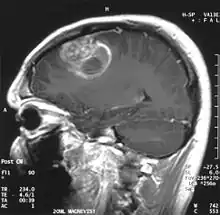

Sagittal MRI with contrast of a glioblastoma WHO grade IV in a 15-year-old -